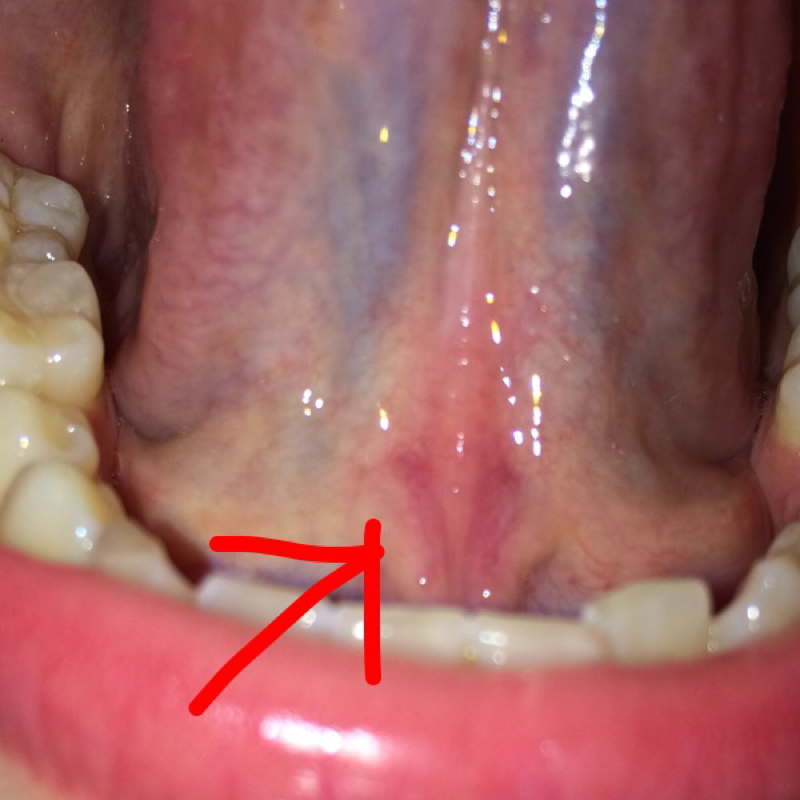

Wieder eine Mandelentzündung? (Schmerzen, Krankheit, Mandeln)